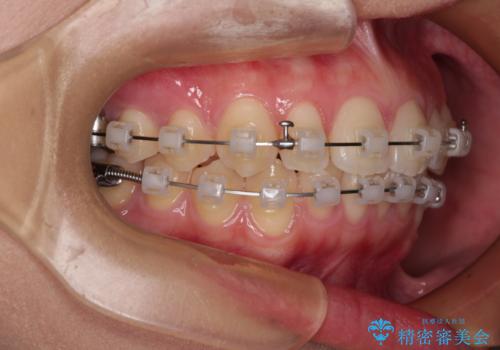

- 矯正装置

- 審美装置

インビザラインでもワイヤー装置でも対応可能でしたが、自己管理の煩わしさの観点から、楽して治療のできるワイヤー装置を選択されました。

抜歯するほどではないものの、やや口元の突出感が気になっていたので、補助装置により上顎臼歯を後方に移動させることで、突出感改善を図ることとしました。